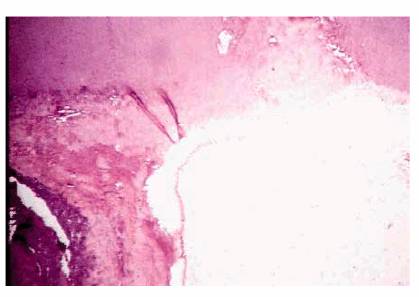

Pulpal Repair

Reparative or irregular dentin is deposited to form a protective barrier for

the pulp tissue and is generally localized to the injury site. This abnormal

dentin forms in response to intense and aggressive pulpal irritants that have

reached the limit of pulp tolerance (eg, erosion, abrasion, caries, dentinal

exposure by fracture, decay or mechanical tooth reduction, traumatic injury,

caustic medicaments, and harmful filling materials).

The histologic appearance of reparative dentin (Figure 19-30) demonstrates dentinal tubules that

are irregular, tortuous, or even absent. The increased thickness of the total

dentin is likely the reason for patients having decreased responses to cold

stimuli as time passes following a dental procedure. Quantitatively, it is

noted that the greater the degree of the "insult" caused by

preparations and restorative materials, the greater the amount of reparative

dentin that forms.

Although this calcified solid wall is considered beneficial and capable of

resisting further episodes of irritation, this healing phenomenon decreases the

ability of the tooth to respond to pulp testing at a later date.

Figure 19-30: Reparative dentin is deposited at specific sites as a result of injury (ie, caries, restorative procedures, attrition, or trauma).